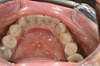

AVANT